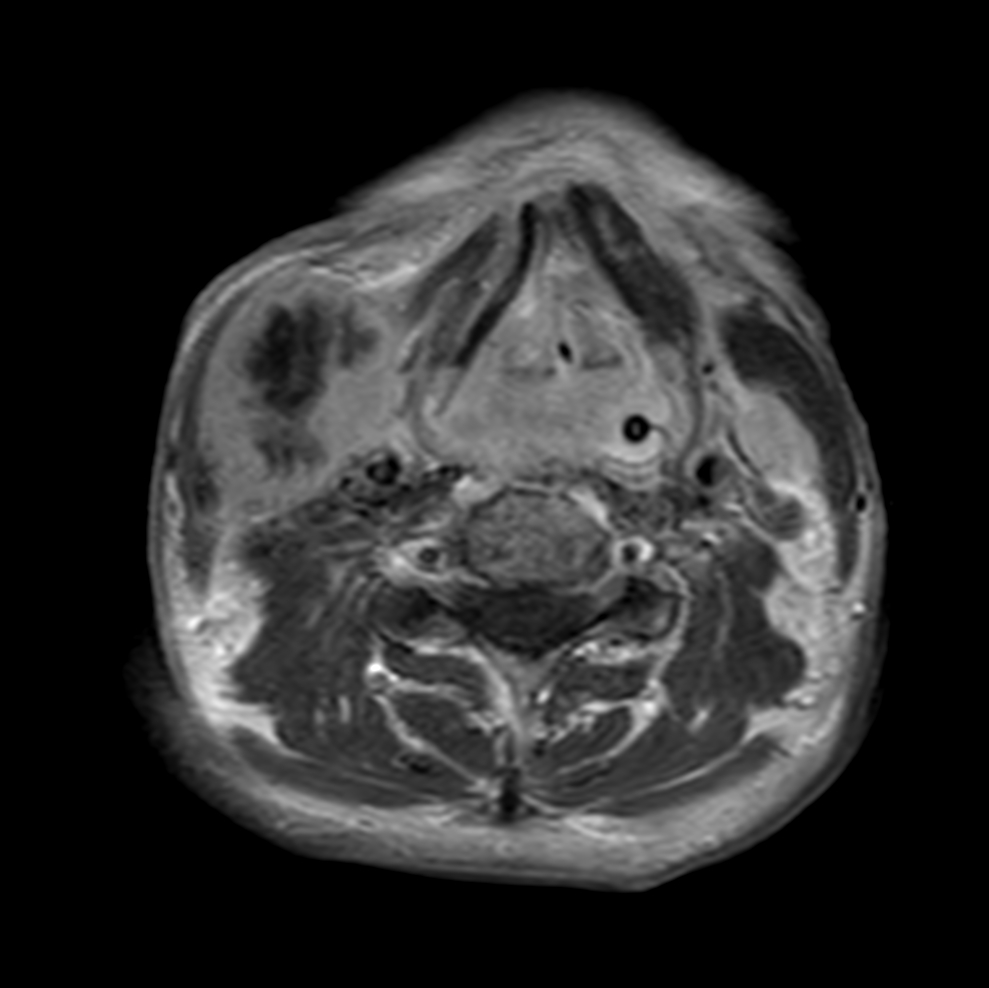

Axial T2w TSE